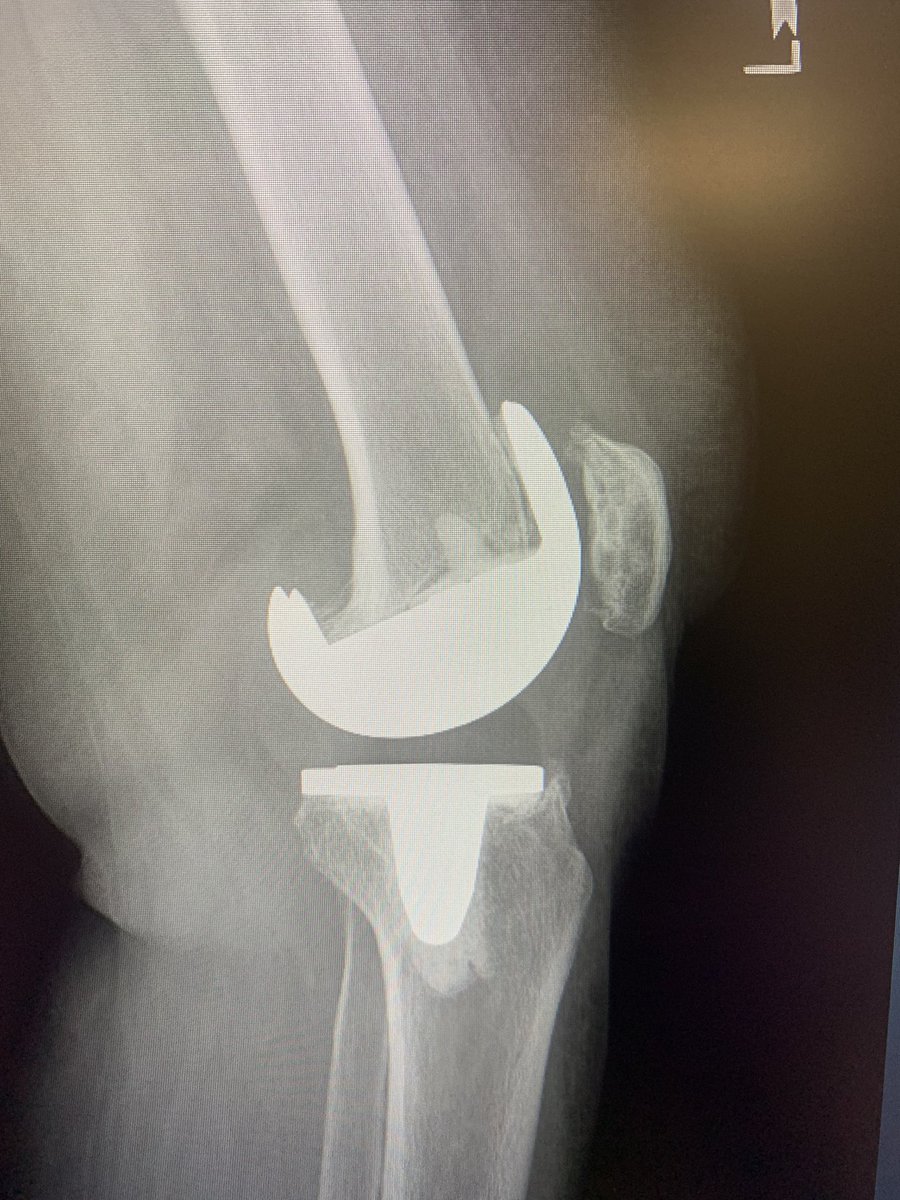

Borrowed this image from @instagram and shared on @LinkedIn Debate has ensued of whether this is real or #AI generated What says #orthotwitter

@generalorthomd @InvictaOrtho